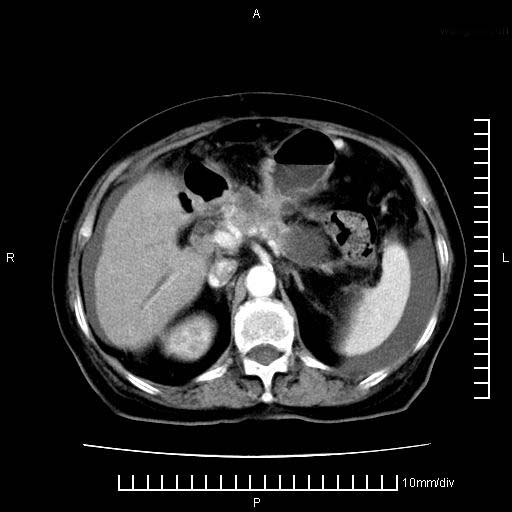

标题: CT28280:腹部增强:女性,80岁

上腹疼痛月余,外院核磁诊断胰腺癌。现临床示右下腹可明显触及包块,可片子上怎么没有看到?

1.胰腺颈体部癌。

2。腹腔积液。

3。右胸腔积液,伴右肺下叶部分萎陷。

4。右肾盂囊肿。

胰腺体部癌累及周围器官,腹膜、粘连

1。胰腺ca伴腹膜腔转移

2。肝左叶低密度灶,考虑转移可能

胰腺体部癌累及周围器官,腹膜、粘连,临床摸到的可能是粘的组织

胰腺结构模糊,胰尾部见囊性包块,周围脂肪密度增高,左肾前筋膜增厚,胸水、腹水。不符合胰腺ca伴腹膜腔转移。考虑胰腺炎伴假性囊肿形成、胸腹腔积液。

右肾盂囊肿。